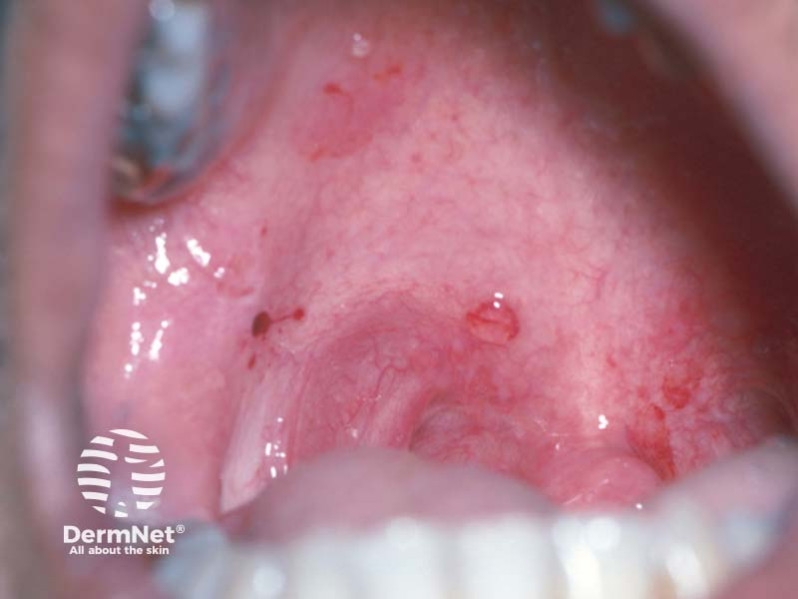

This 40-year-old man has a one-year history of intermittent oral ulcers, which start as blisters. He has now developed blisters and erosions over the chest.

There is an intact blister on the soft palate.

With the development of skin blisters and erosions that follow oral involvement, one must be highly suspicious of pemphigus vulgaris.